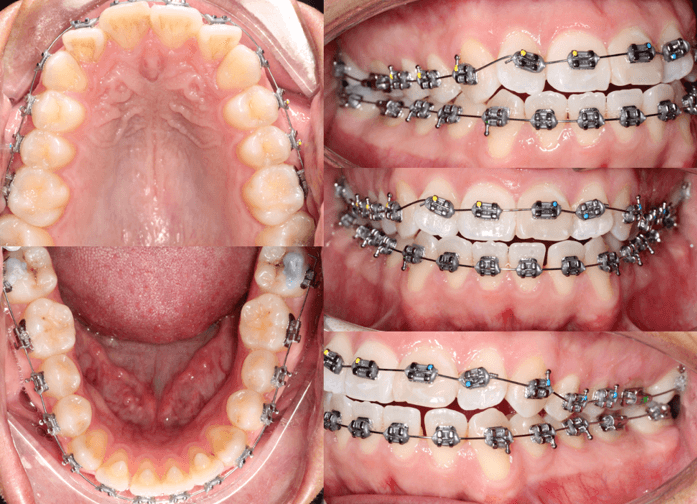

Análisis intraoral

A la evaluacion intraoral presentaba deglusion atipica y una maloclusion molar clase III bilateral, clase II canina del lado derecho y clase III canina del lado izquierdo. Forma de arcada cuadrada en superior y ovoide en inferior. Biprotrusion dental. Presencia de OD 18, 28, 38, 48 erupcionados. Tremas de 3-3 en el maxilar inferior. Mordida cruzada anterior. Overjet de -1 mm. Overbite 0mm.

Fig 2. Fotografias intraorales

Se eligio la prescripcion de brackets MBT slot .022, comenzando unicamente con la colocacion inferior incluyendo primeros y segundos molares. Arco de inicio .14 nitinol cinchado. Spikes de resina en 32, 31, 41, 42 para control de habito y topes oclusales en caras vestibulares del 47-37. El caso se inicio sin la presencia de los terceros molares.

Fig 5. Seguimiento fotografico